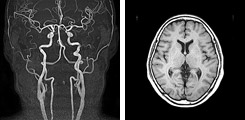

脳ドック:22,000円(がんドック御利用の方:14,300円)

頭部(MRI・MRA)+頚部(MRA)

数種類の脳MRI(磁気共鳴画像)、2方向の脳血管MRA(磁気共鳴血管画像)を、モニター上で回転して立体的に観察し、異常がないか検査します。

レポートによる結果報告となります。